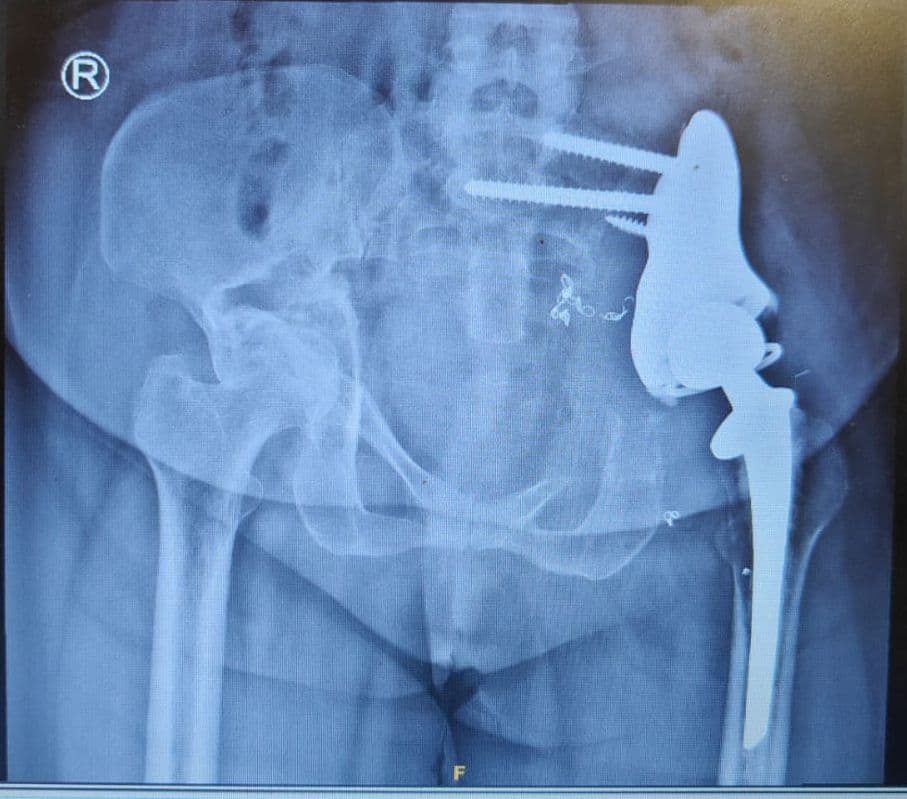

At 65, I never thought I'd dance again due to severe hip arthritis. The total hip replacement surgery was a blessing. The post-operative care and physiotherapy guidance were outstanding. Now I can play with my grandchildren and even attend classical dance performances without pain.

A motorcycle accident left me with multiple fractures in my leg. Everyone said I might never walk properly again. The complex fracture repair and bone reconstruction here proved them wrong. The dedication of Dr. George and his team gave me my mobility back.